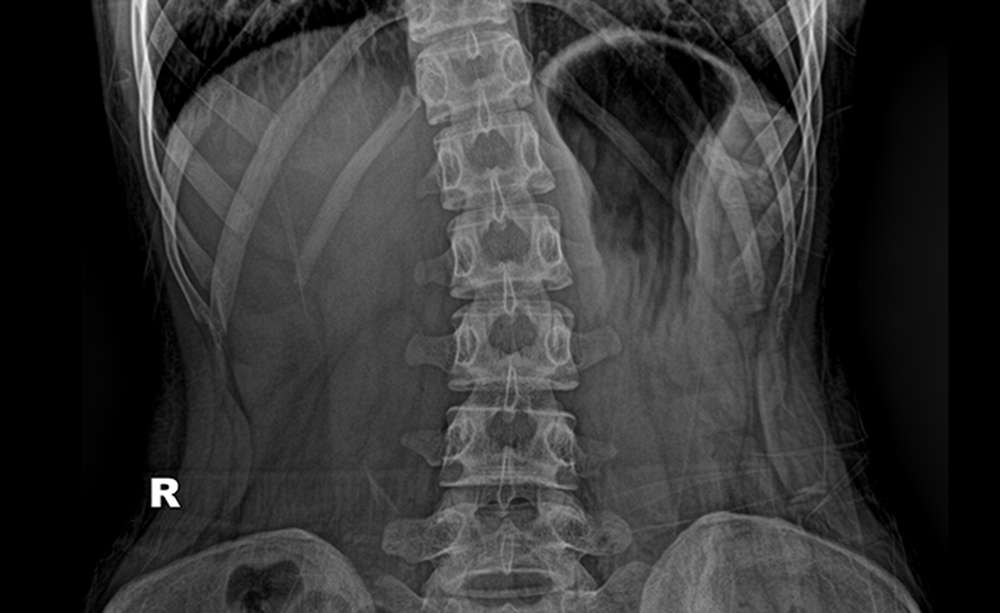

정상적인 척추는 정면에서 봤을 때 일직선이어야 하며, 측면에서 봤을 때 S자 형태를 유지해야 합니다. 척추측만증의 경우에는 정면에서 봤을 때 척추가 옆으로 휘어진 것을 지칭합니다. 서있는 자세에서 양쪽 어깨 높이가 다르거나 등에서 봤을 때 견갑골이 튀어나온 경우, 몸을 앞으로 90도 정도 숙이고 등의 높이가 대칭을 이루지 않고 한쪽이 더 높다면 측만증을 의심해 볼 수 있습니다.